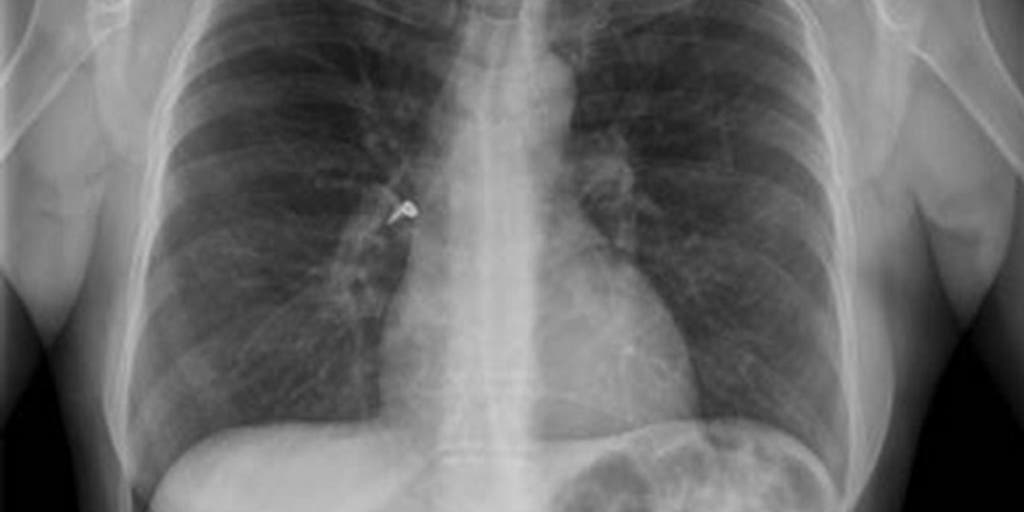

Aspiration can happen when a person has trouble swallowing normally. The food may not move through the esophagus correctly resulting in the sensation of pressure in the chest or food sticking in the throat. This can cause serious health problems such as pneumonia.

Assoc Prof Craig Hacking and Radswiki et al. An ENT can address your issue but it may take time to get an appointment so the best thing to do is to go to the ER. Aspiration can happen when a person has trouble swallowing normally. Barium is a whitish paste that allows the substances to light up under an X-ray so the examiner can determine.